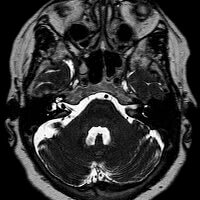

Hématome sous-dural chronique : signes et prévention essentiels

Découvrez tout sur l'hématome sous-dural chronique : ses symptômes, traitements et comment éviter les urgences. Restez informé pour votre santé !

Hématome sous dural chronique : Comprendre et agir efficacement

Découvrez tout sur l'hématome sous-dural chronique : symptômes, diagnostic, traitement et récupération. Restez vigilant et bien informé.